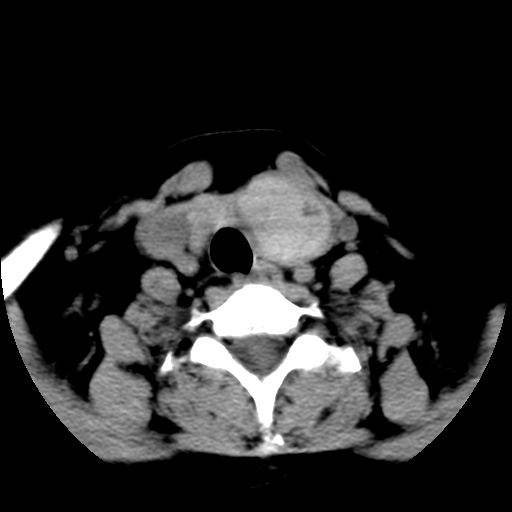

标题: CT25491:女,55岁,发现左侧甲状腺肿块一个月。 [打印本页]

标题: CT25491:女,55岁,发现左侧甲状腺肿块一个月。

女,55岁,发现左侧甲状腺肿块一个月,彩超示:甲状腺多发结节伴左叶结节液化。